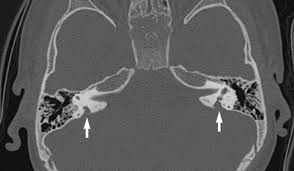

An Axial Non Enhanced Temporal Bone Ct Revealing The Widen Vestibular Download Scientific Diagram

Imaging Findings Of Large Vestibular Aqueduct Syndrome A Ct Scan Download Scientific Diagram